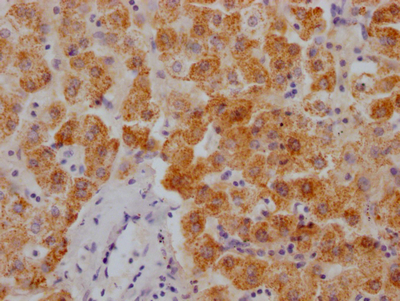

圖片: